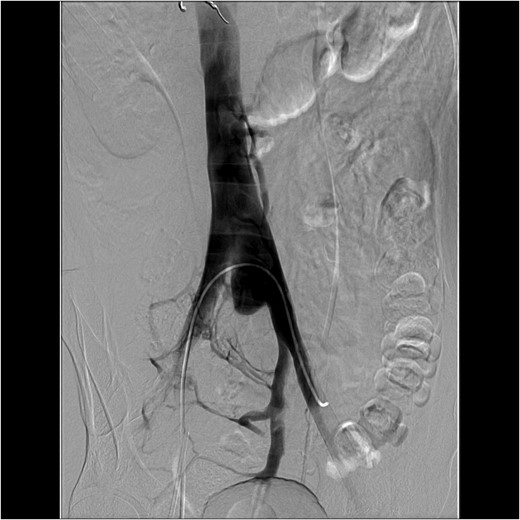

1). Given his hemodynamic stability, we consulted the vascular and interventional radiology teams regarding management. We decided to proceed with visceral arteriogram to control bleeding from the right kidney as well as a venogram to further delineate the suspected venous injury (Fig.

2).

The visceral arteriogram demonstrated extravasation from the right adrenal artery and superior pole of the kidney, both of which were embolized with microcoils. Post-embolization angiography demonstrated no further evidence of active extravasation. There was no injury to the aortic bifurcation. A venogram was then performed, which demonstrated a 2.8 cm pseudoaneurysm arising from the proximal portion of the left common iliac vein with involvement of the base of the IVC without active extravasation. There was no involvement of the right common iliac vein. The patient continued to be hemodynamically stable so the decision was made to observe him. After an initial hemoglobin drop from 14.3 to 6.9 g/dL within the first 48 h, he stabilized between 8 and 9 g/dL after two units of packed red blood cell transfusion and then remained hemodynamically stable throughout his stay. He was initiated on aspirin and therapeutic heparin for his carotid dissection on hospital Day 2 and underwent a cerebral angiogram and right internal carotid stent placement on hospital Day 14. A CT venogram on hospital Day 16 demonstrated a decrease in size of the pseudoaneurysm, and a stable prevertebral and pelvic retroperitoneal hematoma (Fig.

Figure 2:

An interventional radiology angiogram and venogram on Day 1 showed a 2.8 cm pseudoaneurysm in the proximal portion of the left common iliac vein. There was no involvement of the base of the IVC and no active extravasation.